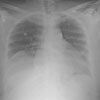

Vital signs are normal. Breaths sounds are diminished at both lung bases. No abdominal masses are noted; however, the epigastric area is tender on deep palpation. Levels of serum glucose and amylase are elevated (191 mg/dL and 784 U/L, respectively). Other laboratory results are normal. The next day, the lipase level rises to 380 U/L. The chest film is shown.

Figure 1

This patient had a sliding hiatal hernia. The double shadow in the right mid and lower lung field of the chest radiograph represents the herniated stomach, which contains gas (A, arrows).